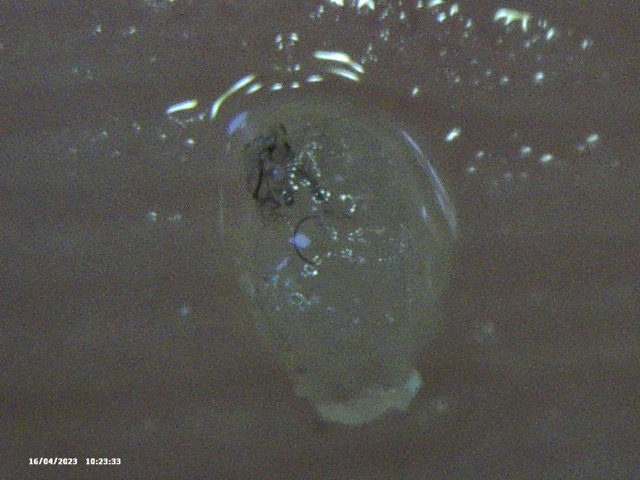

Below is the selection of recent images that I showed him. In isolation they look like they could be ‘anything’ – but with the context of my described condition, and the consistency of objects being extracted, I thought this might, at a minimum be considered ‘not right’ and warrenting further investigation. Silly me.

Image Notes:

- That is my fingerprint in the background.

- All objects are recent and have been extracted over the last 2 weeks

- I simply cannot see some of these objects – however I can feel them, ROCK HARD.

- This is a small selection of what I’m taking out of my skin where I am feeling movement, there are literally 100’s of these things. Imaging them become’s pointless as they are similar.

- Average Distance between fingerprint ridges is 0.15mm for a sense of scale.